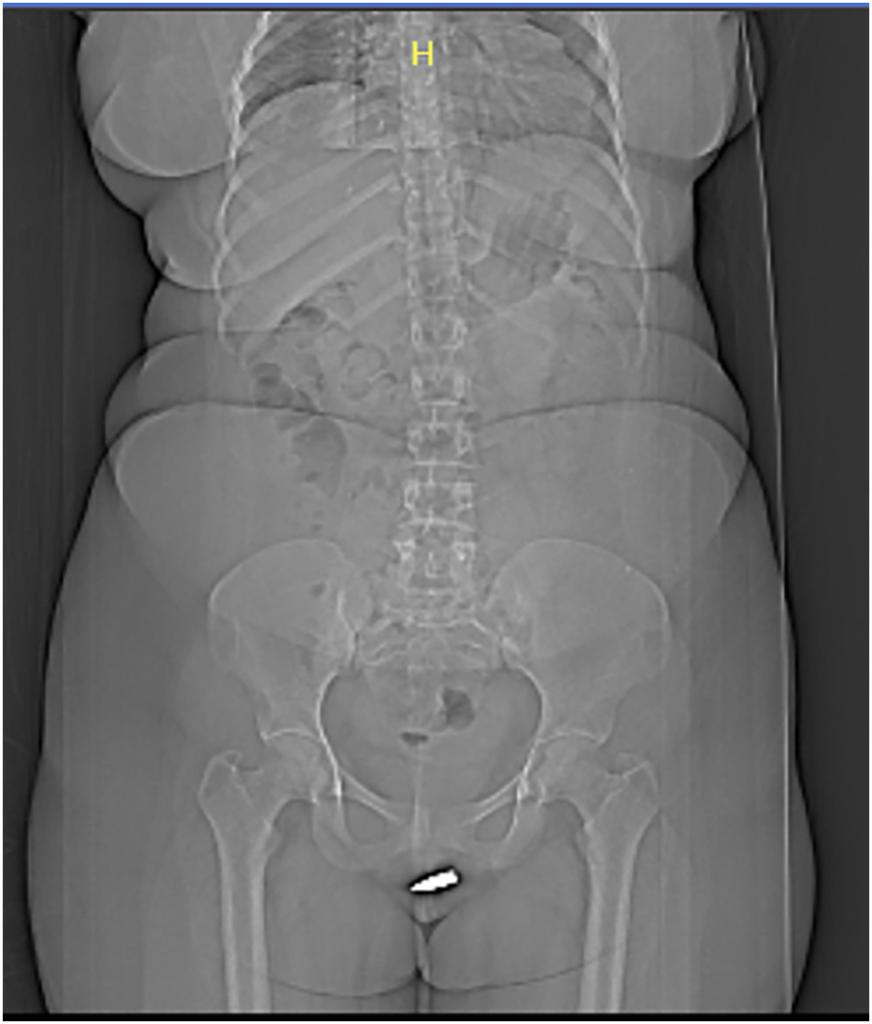

Η γυναίκα φέρεται να χαλάρωνε στο σπίτι της όταν χτυπήθηκε από την αδέσποτη σφαίρα. Η περίπτωσή της αναφέρεται στο International Journal of Surgery Case Reports και η εικόνα από την ακτινογραφία φαίνεται σαν η γυναίκα να έχει κάνει piercing, στην συγκεκριμένη περιοχή. «Από όσο γνωρίζουμε, αυτός είναι ο πρώτος παράξενος τραυματισμός από σφαίρα που διεισδύει στην περιοχή του αιδοίου (το εξωτερικό μέρος των γυναικείων γεννητικών οργάνων) και η σφαίρα συγκρατείται σφαίρα στην κλειτορίδα», έγραψαν οι συγγραφείς της μελέτης.

Σύμφωνα με τη μελέτη, η 24χρονη άγνωστη ασθενής χαλάρωσε στο σπίτι της, όταν ξαφνικά μια αδέσποτη σφαίρα πέρασε από το ταβάνι της και τη χτύπησε στα γεννητικά όργανα. Αιμόφυρτη η γυναίκα πήγε στο νοσοκομείο Ερντογάν στο Μογκαντίσου, όπου μια αξονική τομογραφία αποκάλυψε ότι το βλήμα είχε κολλήσει μέσα στην κλειτορίδα της. Από όσο γνώριζαν οι συγγραφείς της μελέτης, αυτή ήταν η πρώτη τέτοια περίπτωση.

(Φωτό: International Journal of Surgery Case Reports)